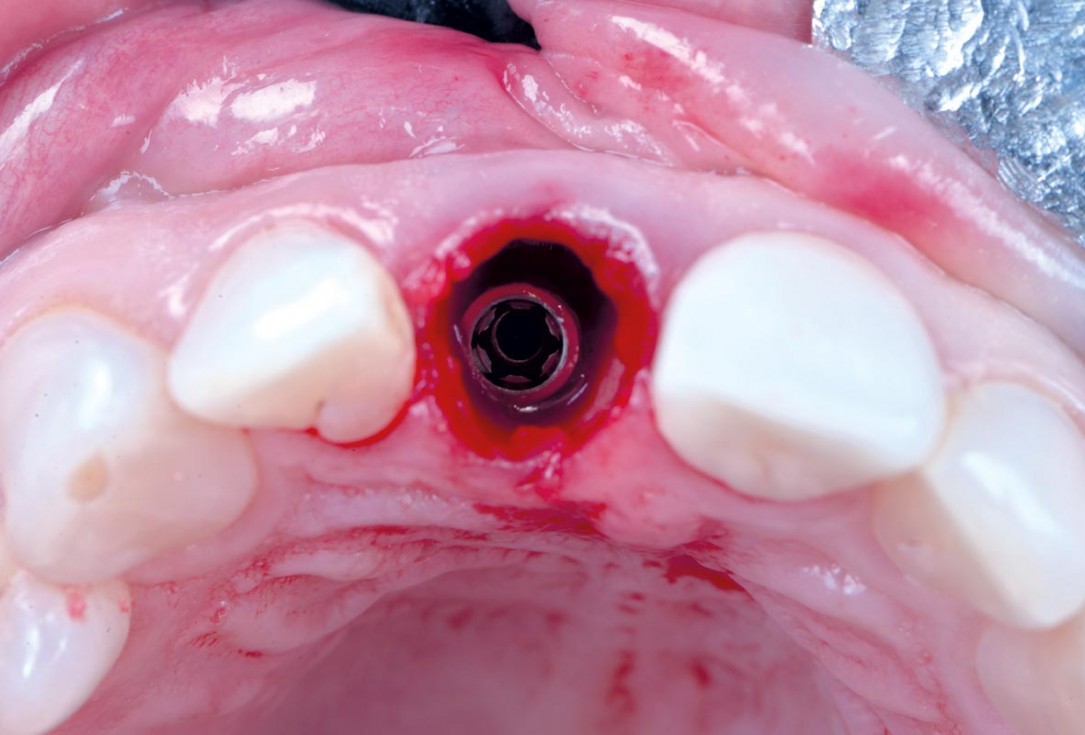

cerabone® and mucoderm® for immediate implantation in the aesthetic area - Dr. D. Robles

Initial clinical situation - Central incisors with dental destruction and periapical pathology